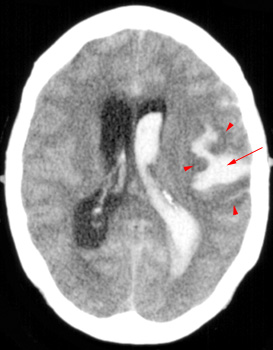

Question 7: Given the following head CT, the most likely diagnosis is: